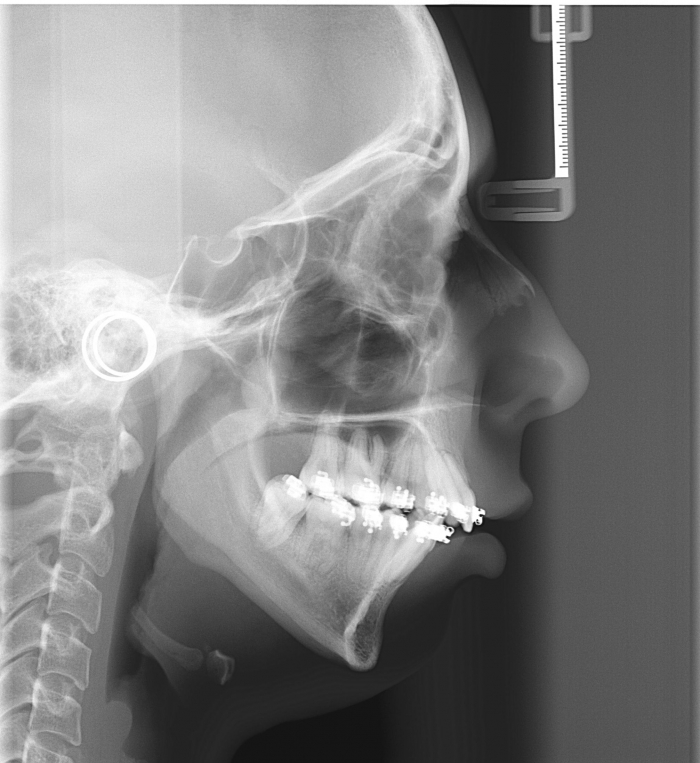

Telerradiografia inicial

Telerradiografia após a cirurgia 2018